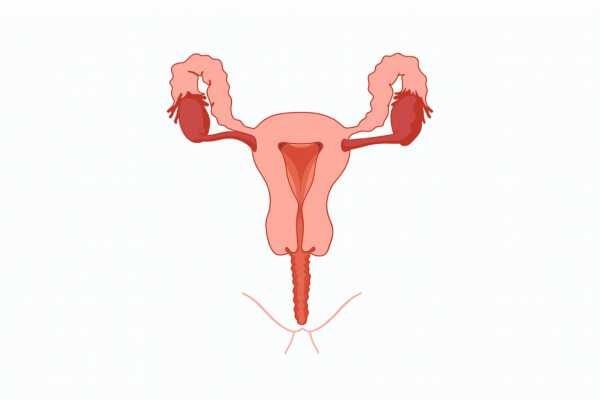

Discover the wonders of the human body, from its fundamental elements to the intricate systems that sustain life. This section explores the anatomy, physiology, and functions of various body parts, providing insights into our movements, thoughts, emotions, and interactions with our surroundings.